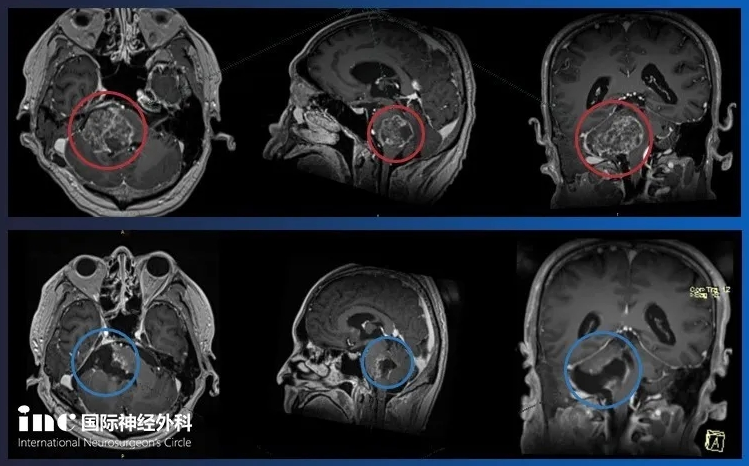

巨大脑膜瘤患者感谢INC和巴特朗

巨大脑膜瘤患者感谢INC和巴特朗菲教授,说起这位巴特朗菲范教...